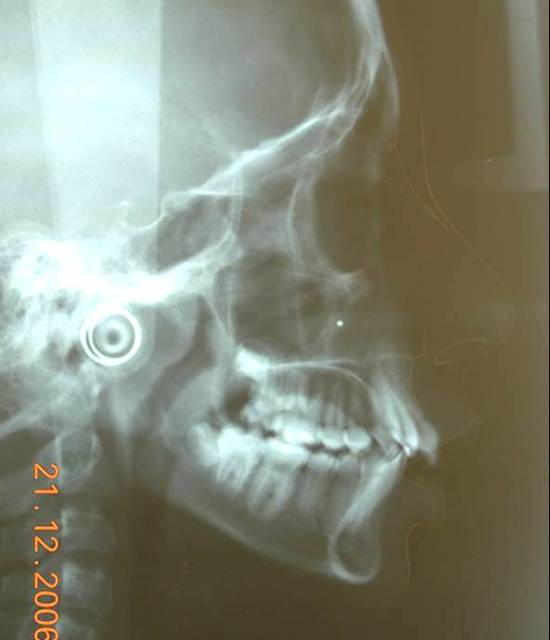

Je crois cette fois ca va marcher. Il s'agit d'une jeune fille de 12 ans, origine franco-libanaise, deja reglee depuis qqs mois. Classe II1 dentaire. Une demande majeure pour la patiente et sa maman: Les dents du haut sont trop en avant, il ne faut surtout pas les avancer ou les garder comme ca!!!

3 uk1wzr - Eugenol

pour ce cas:

classe II squelettique(responsabilite mandibulaire),cl II dentaire,petite ddm,constriction de arc sup,flaring des incisives sup,face moyenne etroite,mesiodivergent

Merci pour tous ces messages qui montrent que vous estes tous sensibles a cette retrogenie, et surtout votre concepte anti-extraction. Figurez vous et c'etait exactement mon point de vu de depart car j'ai pris ce cas comme un type caucasien, europeen et j'ai fait le deverrouillage necessaire sous toutes ses formes mais la mandibule n'a pas voulu avancer du tout, meme pas un mm!! Je crois que la typologie ethnique, sagittal et vertical, de cette patiente ne permettait pas l'avancement mandibulaire par contre l'avancement alveolaire, bonjour les degats!!!!! Une autre difference, dans un pays chaud une fille de 12 ans c'est comme une fille de 14 ans dans un pays froid, il ne faut pas fantasmer sur ce que je dits mais c'est la verite?!!